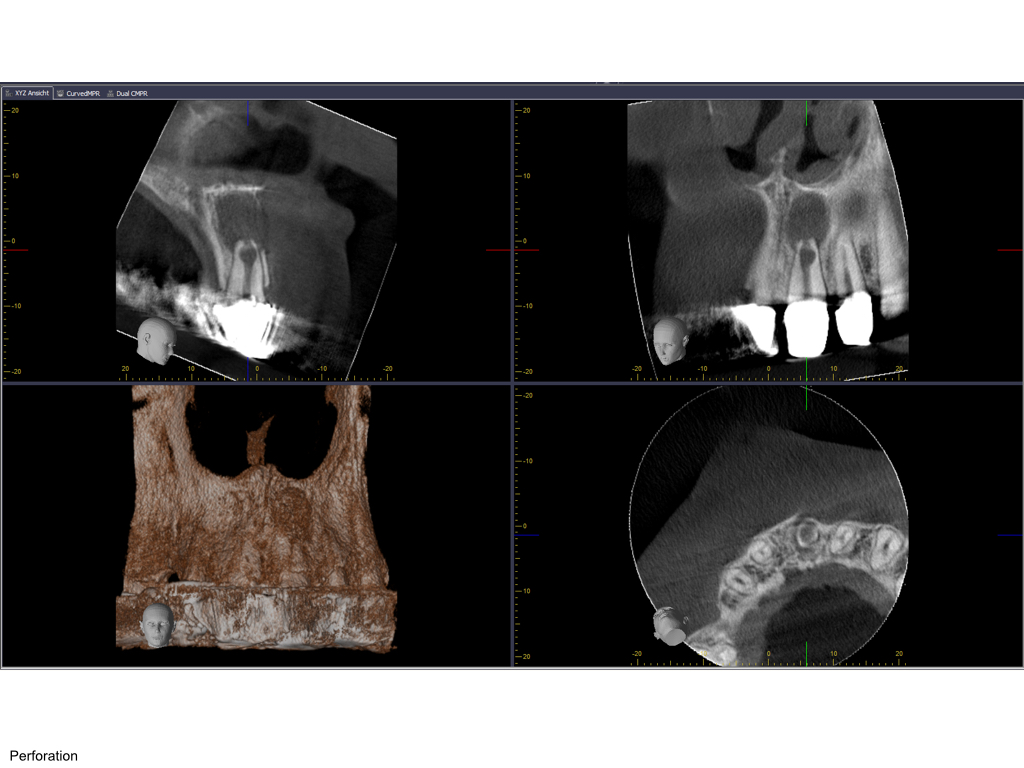

Saving hopeless teeth (37)